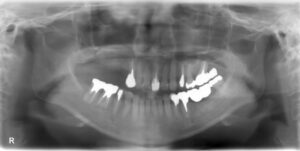

上顎臼歯3本欠損症例

BEFORE AFTER 54歳女性/上顎臼歯3本欠損/インプラント埋込手術 【治療内容】 右上第二小臼歯の被せものの脱…